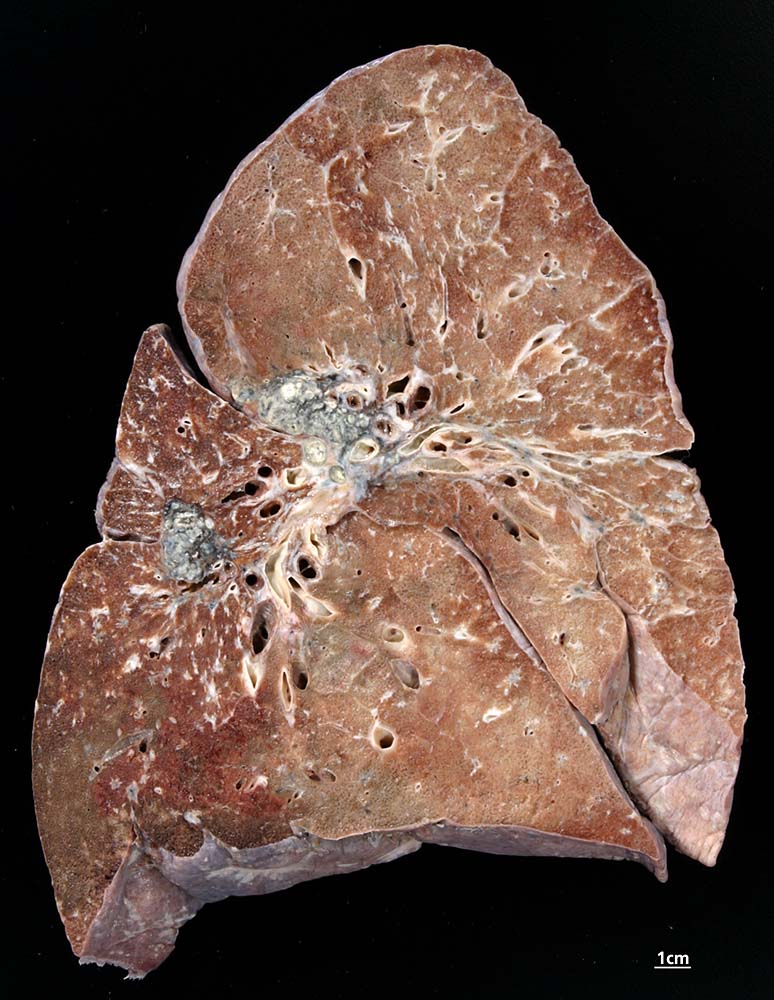

Lungensarkoidose

Graugelbe Granulome in hilären Lymphknoten und im Lungenparenchym bevorzugt peribronchiolär.

Sarkoidose Stadium IV. Erstdiagnose vor 5 Jahren. Lungenparenchymbefall beidseits und bihiläre Lymphadenopathie. Normale Lungenfunktion. Steroiddauertherapie.